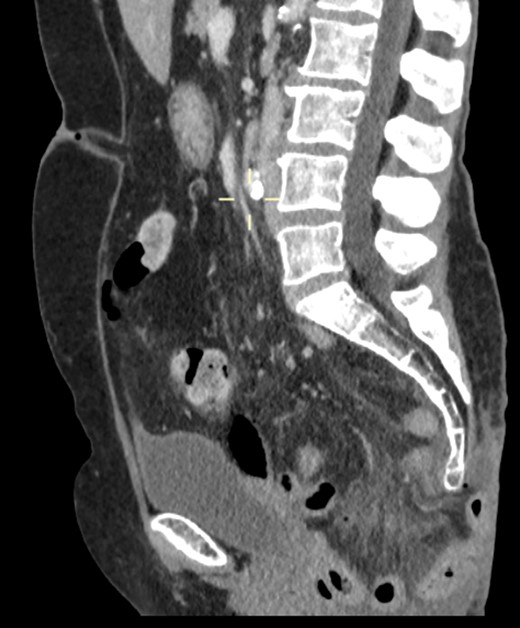

On examination, she was febrile. Her abdomen was generally tender. Bowel sounds were present and up to that time her stoma was working. Her perineal hernia was red and tender. Her initial CXR (Fig. 1) did reveal a sliver of gas underneath her right hemidiaphragm and in keeping with her abdominal findings she progressed to further imaging. CT abdomen pelvis with contrast showed pneumoperitoneum (Fig. 2) with ‘a tiny pocket of air is also seen adjacent to a loop of bowel in the pelvis posterior to the bladder’. ‘Exact site of perforation has not been demonstrated but could possibly be in the bowel loops in the perineum’ (Figs 3 and 4).

Sagittal view showing small bowel loops in pelvis with perineal hernia.